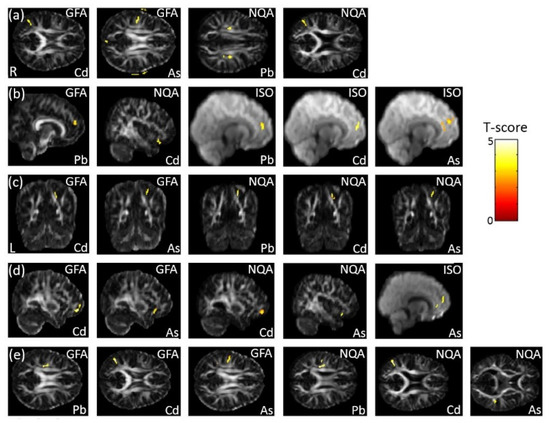

3.7. The Association Between Heavy Metals and GQI